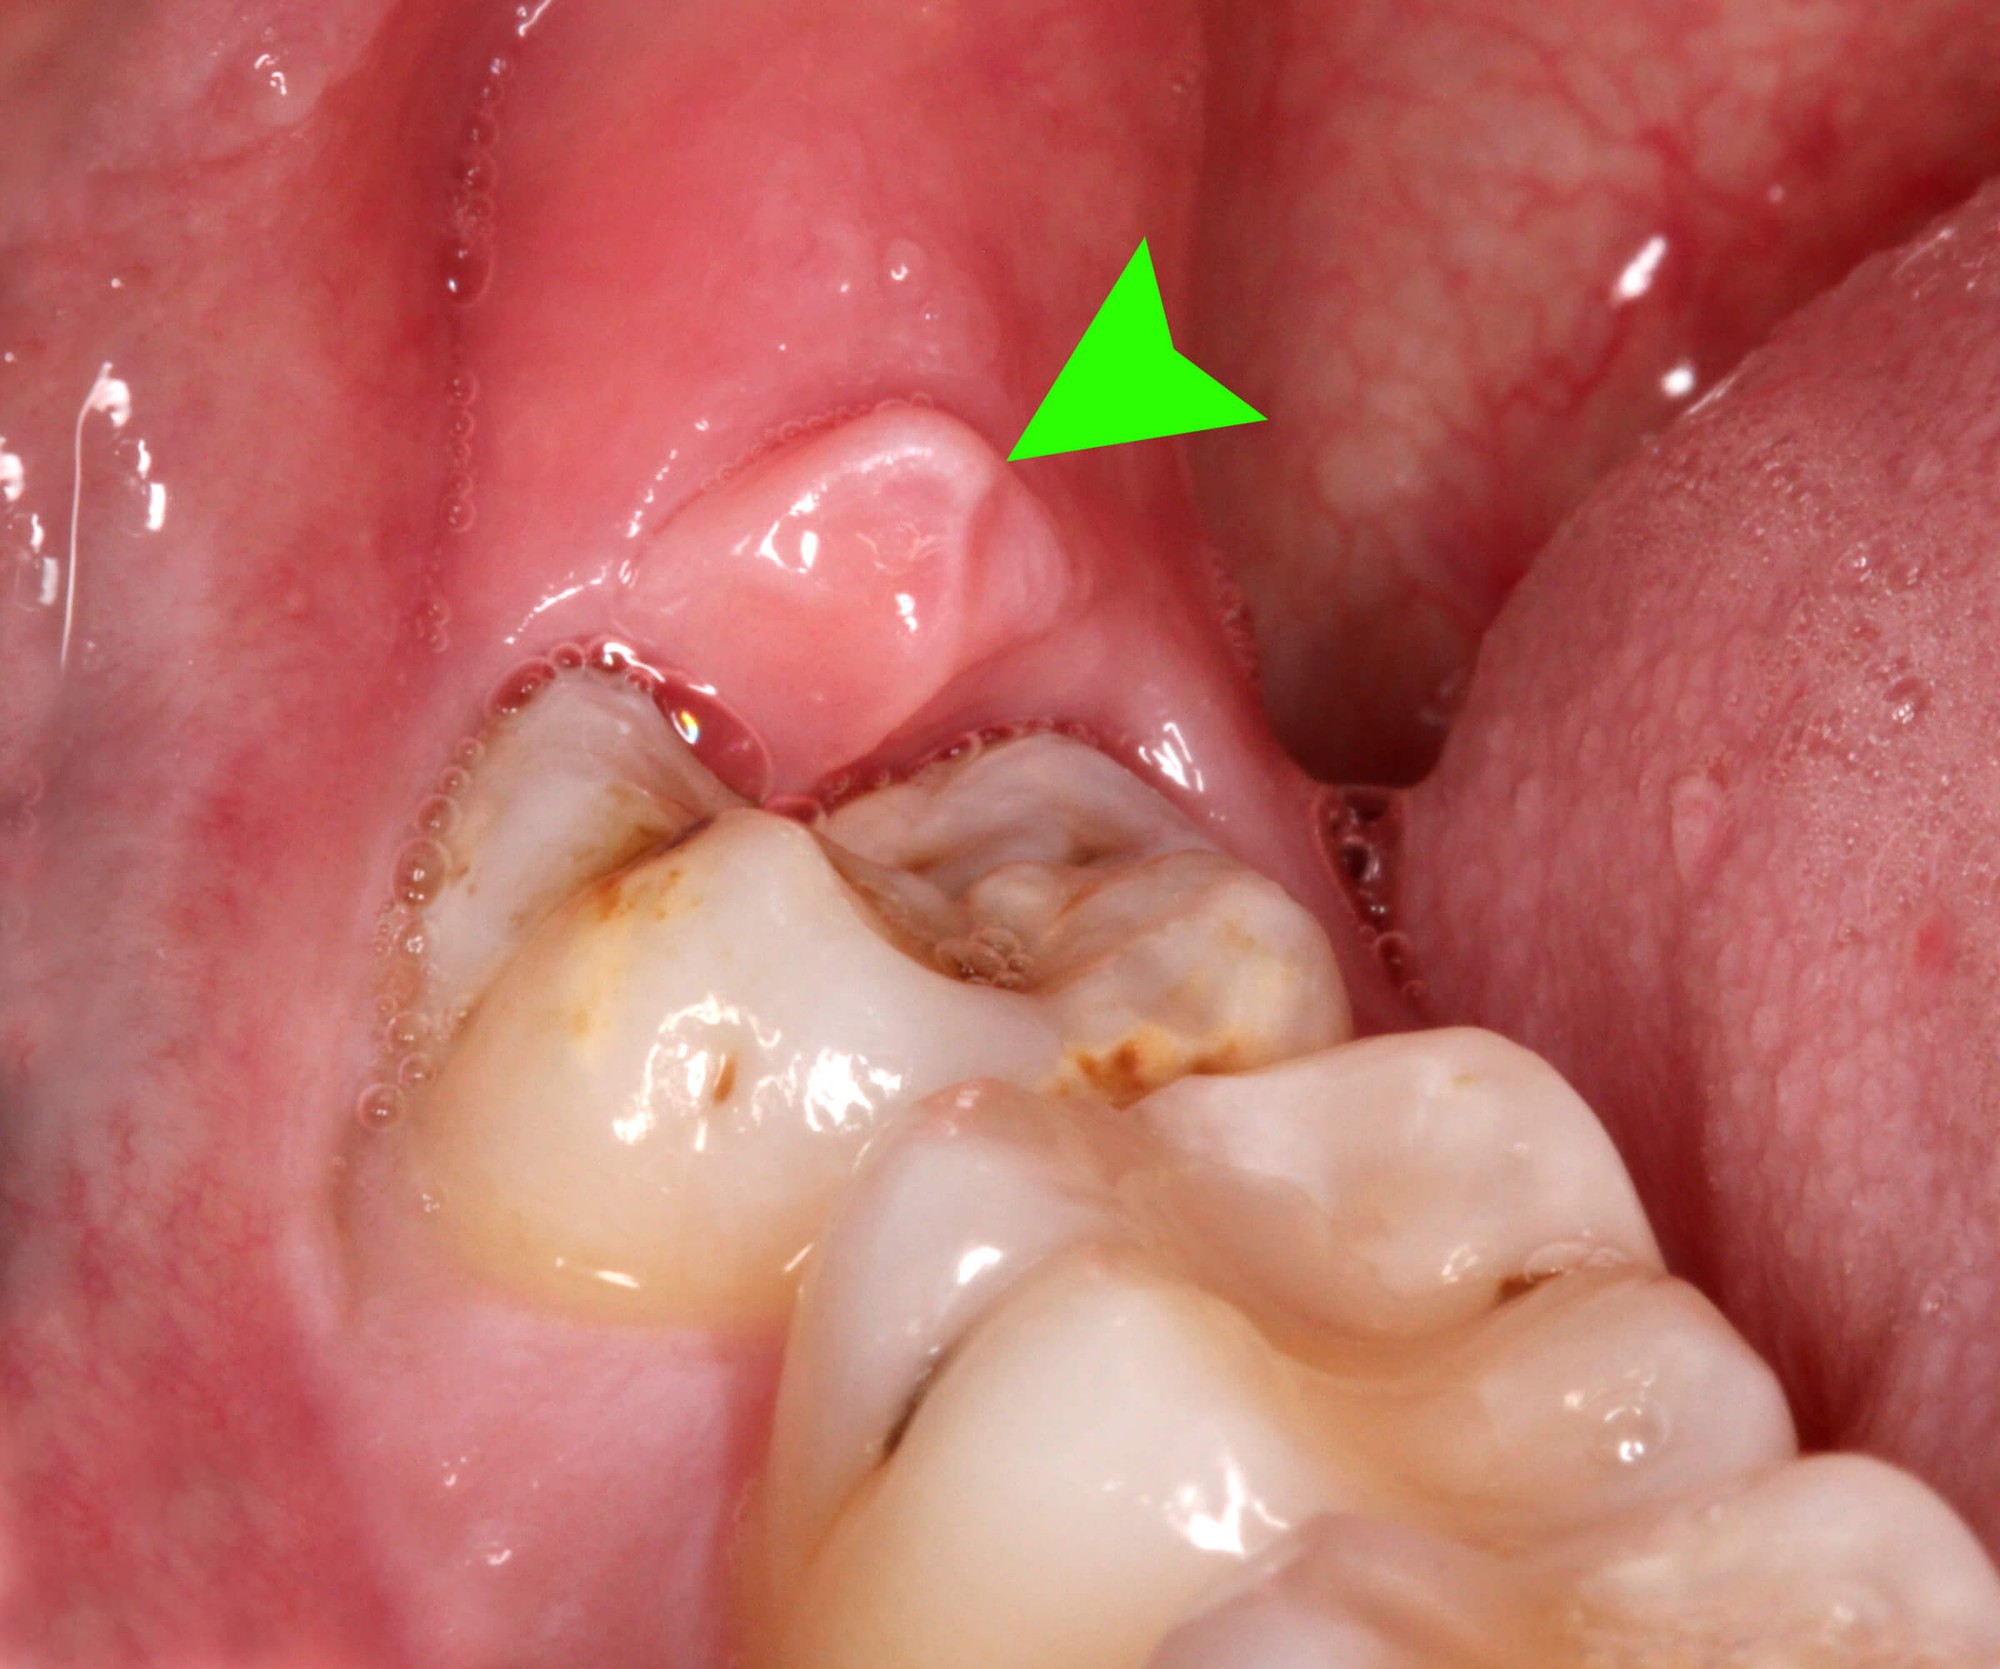

Old  Arrow Thời điểm nào chớ dại nhổ răng khôn

Thời điểm để nhổ răng khôn khá quan trọng. Nhổ răng khôn là một việc mà rất nhiều người sẽ phải đối mặt sau 20 tuổi, tuy nhiên, có những thời điểm cần tránh đi nhổ răng vì có thể dẫn đến những biến chứng gây ảnh hưởng lớn tới sức khỏe.

Nhổ răng khôn vốn là một loại tiểu phẫu thường gặp khi răng khôn bị mọc lệch, gây nhiễm trùng, viêm mô mềm xung quanh. Tuy vậy, bạn cũng cần lựa chọn đúng thời điểm đi nhổ răng khôn để tránh gây ra các ảnh hưởng nghiêm trọng tới sức khỏe. Dưới đây là 4 thời điểm cần tránh nhổ răng khôn để hạn chế gặp phải những biến chứng nghiêm trọng.

Người đang bị viêm răng lợi

Trong đó, những người đang bị viêm răng, viêm lợi thì không nên nhổ răng vì dễ gây viêm nhiễm nặng. Đặc biệt trong quá trình khâu, nếu không vệ sinh kỹ sẽ dẫn tới những biến chứng nguy hại về sau.